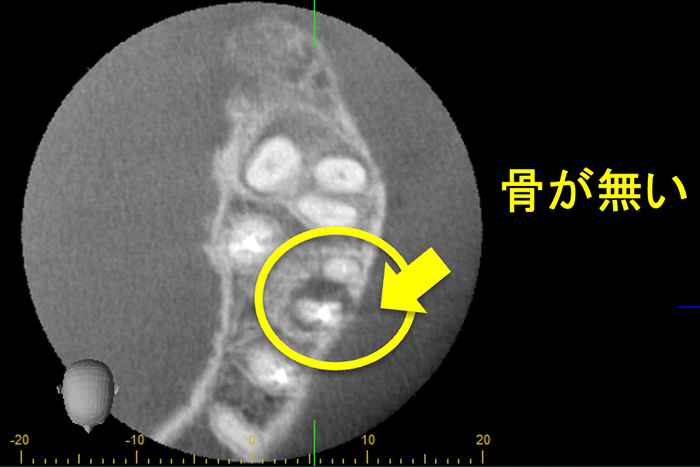

他院にて、抜歯といわれ、セカンドオピニオン目的に来院されました。

①自覚症状なし・歯肉にサイナストラクト(排膿路)あり

②初診時レントゲン解説

・歯根周囲に透過像(黒い影)あり

・遠心根根管充填:アンダー